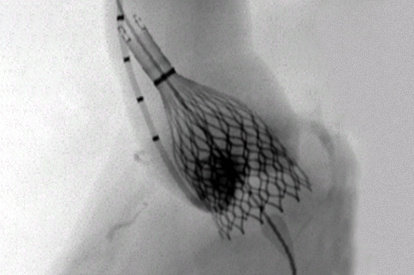

The ANGIO Mentor simulator is an essential tool for clinicians to practice and acquire the skills needed for performing endovascular interventions. Trusted by medical associations, hospitals, training centers, and the medical device industry globally, it provides trainees with realistic clinical settings to practice endovascular interventions using fluoroscopic and ultrasound guidance.

Offers true-to-life simulation of the clinical environment, including advanced imaging modalities like fluoroscopy/echocardiography, hemodynamic monitoring, medications, and interventional devices

TAVI (Transcatheter Aortic Valve Implantation) Module

ASD-PFO Closure Module

LAA Closure Module